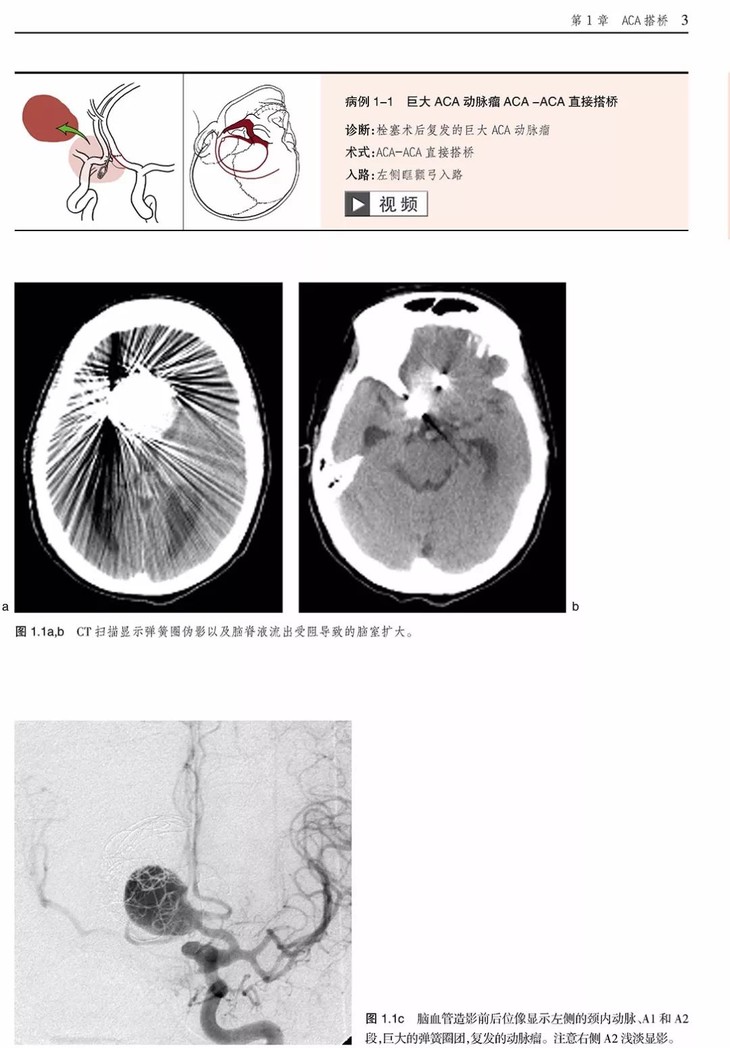

《脑血运重建彩色图谱:解剖、技巧及病例》主要介绍了脑血运重建手术的各种技巧和临床应用。这项技术是世界著名的亚利桑那州凤凰城巴罗神经病学研究所的外科医生首创的。每个步骤都以术中照片及精美的解剖图呈现,以帮助神经外科医生掌握复杂的显微外科解剖及微妙的外科技巧,从而用于治疗脑卒中潜在发作以及其他脑缺血疾病。

•描述了如何成功实施诸如烟雾病、血管内治疗后复发动脉瘤、巨大动脉瘤,以及椎动脉供血不足及重度狭窄的脑血运重建

•治疗临床病例的描述过程中展示了每种重建手术相关的血管解剖